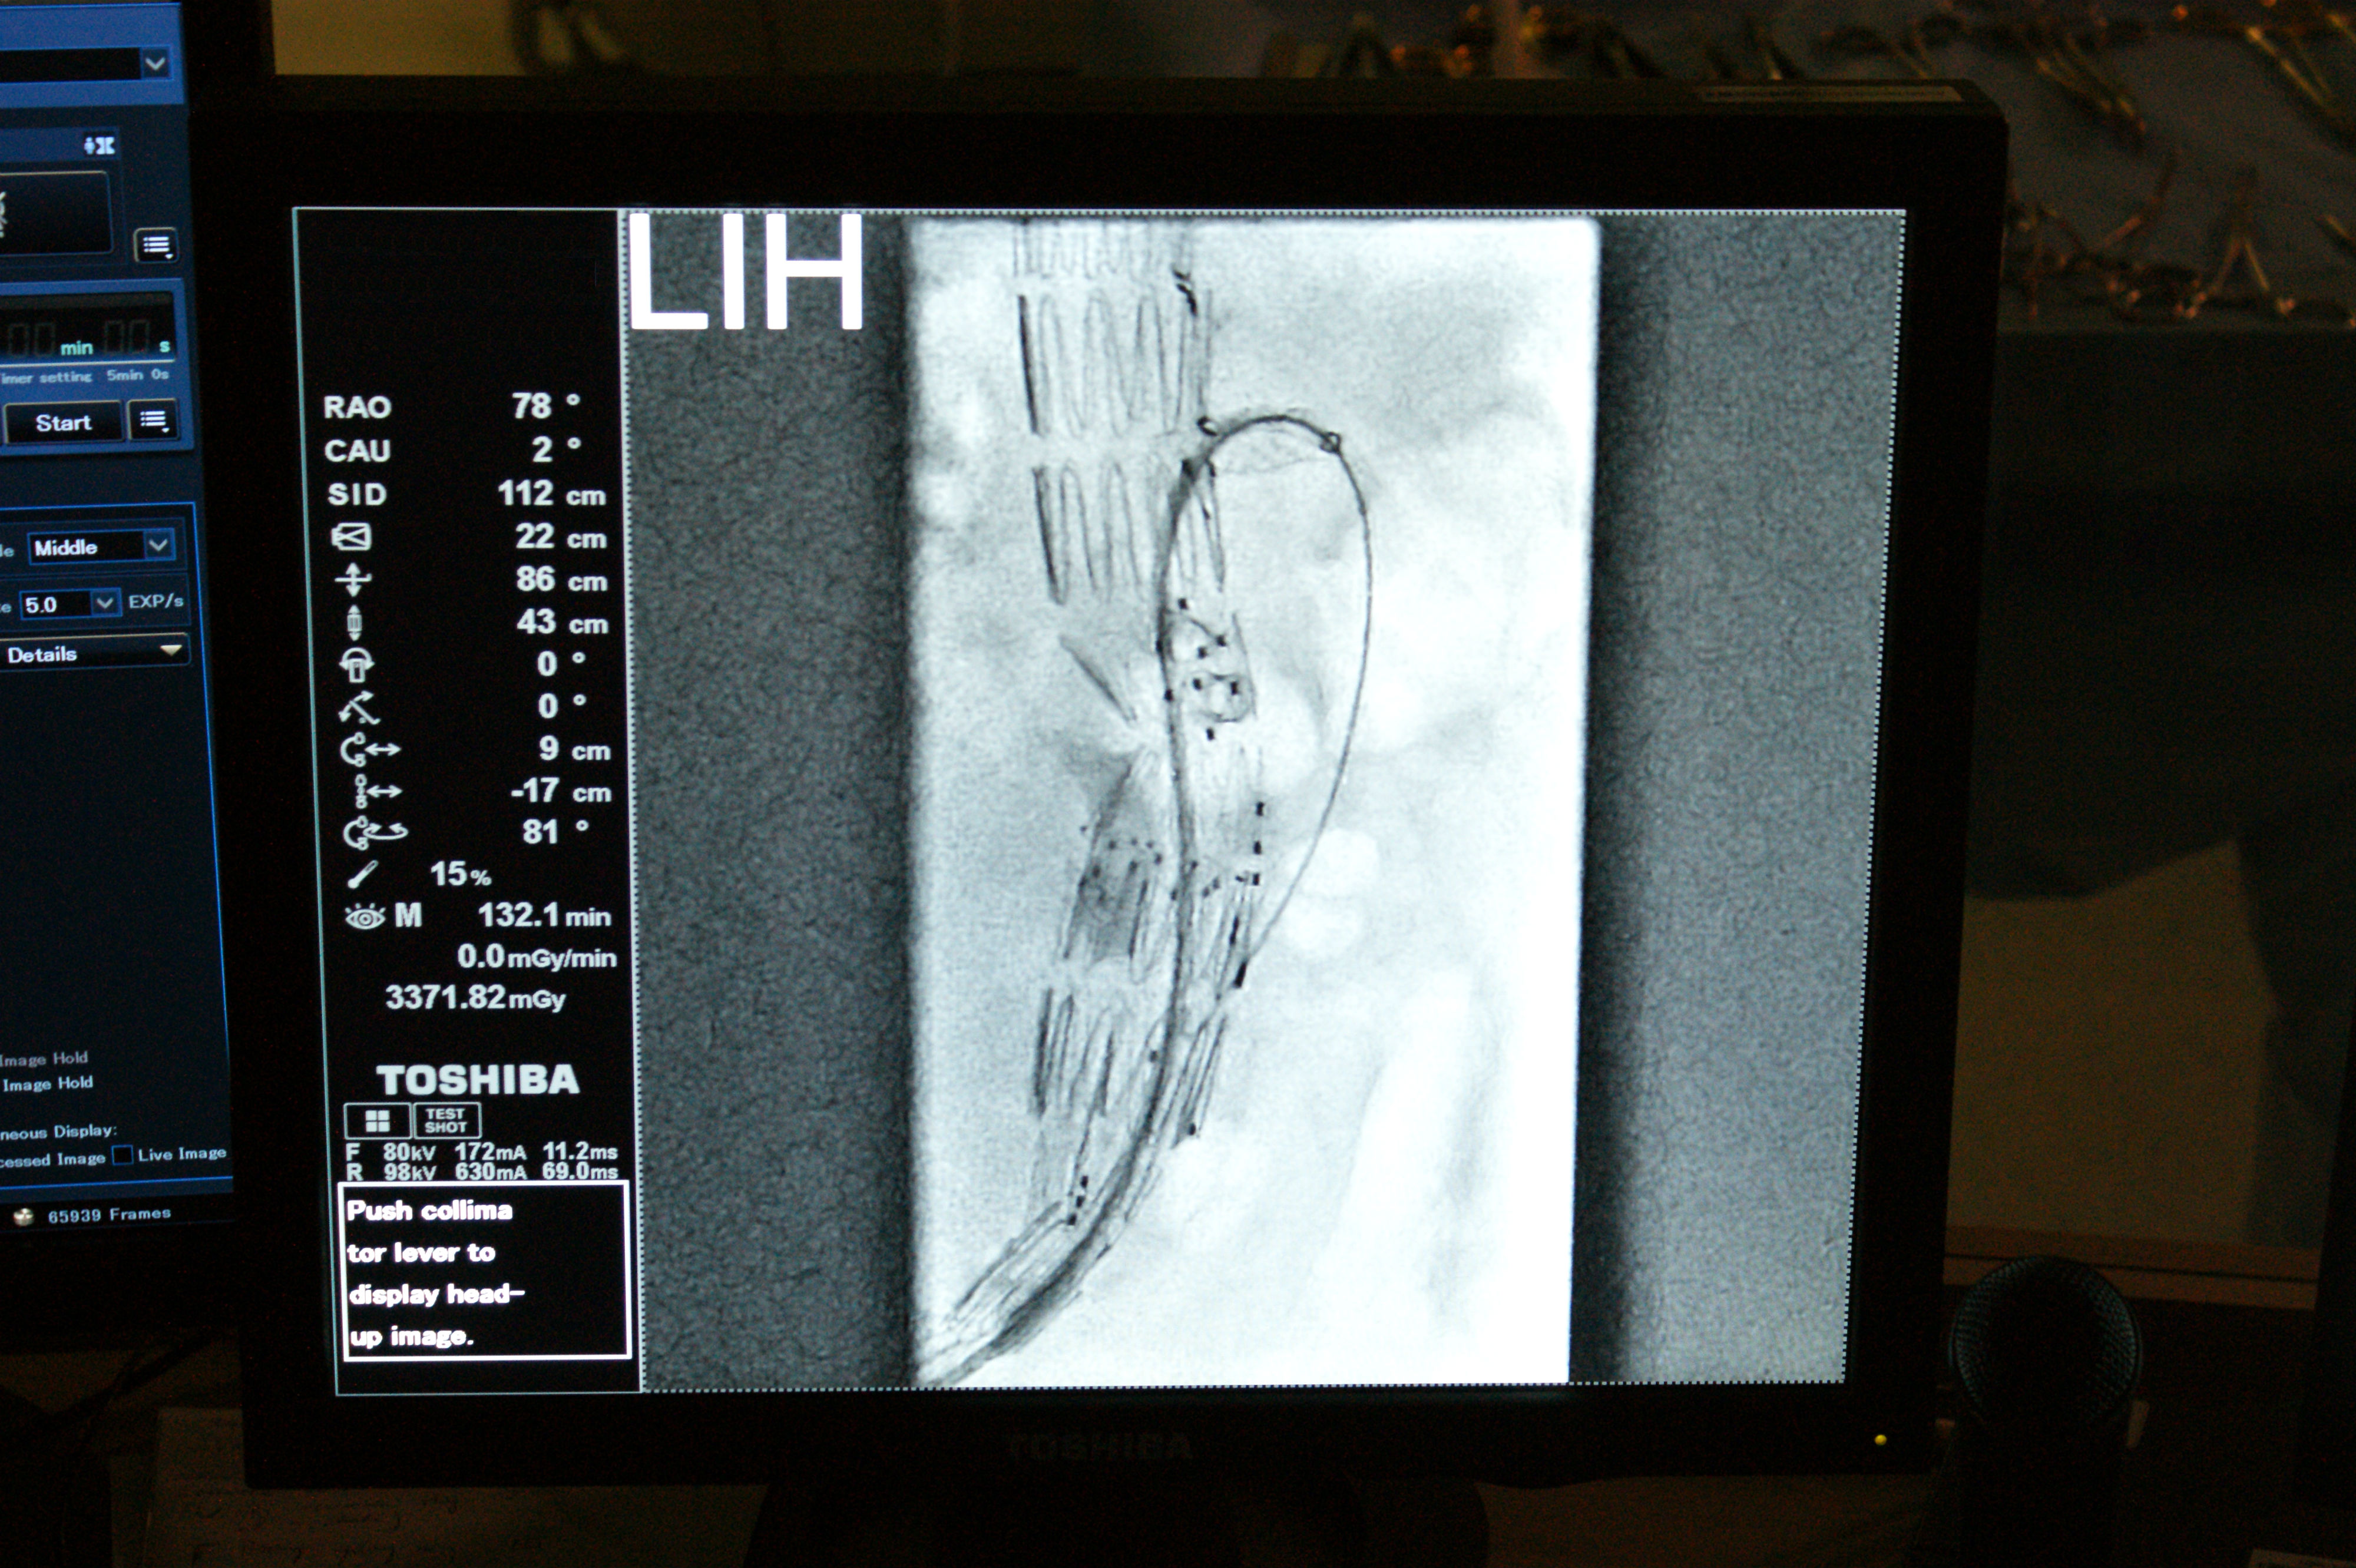

Po znieczuleniu u pacjenta okolicy pachwinowej odsłonięty został otwór owalny w powięzi, przez który powierzchnioważyła odpiszczelowa łączy się z żyłą udową. Tak to wygląda w prawidłowych warunkach anatomicznych. W opisanym przypadku z żyłą udową łączyła się nietypowa, krótka żyła z kilkoma wąskimi dopływami. Nie było charakterystycznego szerokiego pnia żyły odpiszczelowej. Odcięto od żyły udowej dopływ imitujący żyłę odpiszczelową. Wycięto żylaki podudzia. Do odsłoniętego pnia żyły odpiszczelowej poniżej kolana wprowadzono metalowy zgłębnik (linkę z końcówką w formie grzybka), za pomocą którego usuwana jest podskórnie żyła. Koniec zgłębnika ujawnił się w pachwinowym odcinku żyły udowej. Na tej podstawie rozpoznano nieprawidłowość anatomiczną, polegającą na nietypowym umiejscowieniu ujścia żyły dopiszczelowej. Miejsce to zidentyfikowano po wykonaniu dodatkowego cięcia na przyśrodkowej powierzchni uda. Wycofano zgłębnik z żyły udowej. Odcięto żyłę odpiszczelową od żyły udowej i powiązano kikuty. Za pomocą zgłębnika, podskórnie usunięto pień żyły odpiszczelowej. Po zszyciu ran założono uciskowy opatrunek na całą kończynę. Po krótkim odpoczynku pacjent powrócił do domu. Po tygodniu z zagojonych ran zdjęto szwy. Przez trzy tygodnie miał, stopniowo ustępujące, niewielkie dolegliwości.